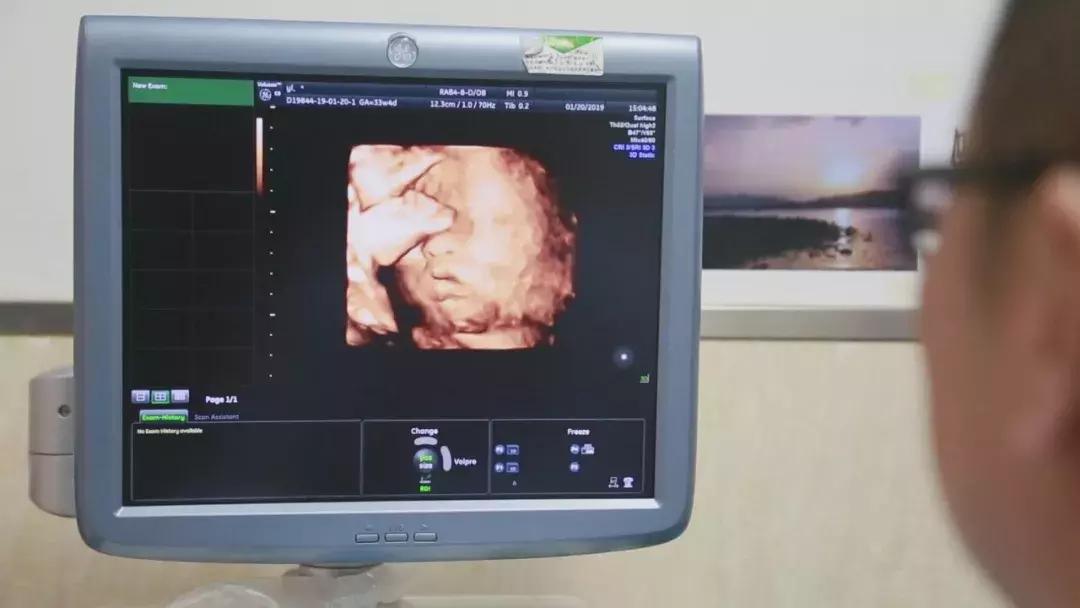

冷冻胚胎植入子宫孕育新生

在对移植子宫连续监测后,为提高胚胎移植成功率,专家团队采取中西医结合的方法,改善杨华子宫内膜情况,为胚胎着床做好准备。2018年6月13日,妇产科王西林教授实时监测超声,在超声“慧眼”精确指引下,妇产科黄艳红教授小心翼翼地将冷冻胚胎植入移植的子宫内。14天后,复苏胚胎着床,杨华成功妊娠,这已是第五次尝试。妊娠早期,杨华出现妊娠剧吐、先兆流产的症状,妊娠中晚期出现胎儿生长受限,先后4次住院进行保胎等治疗。